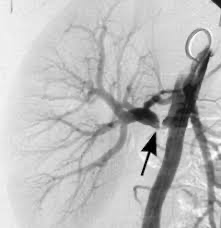

Catheter Angiography (DSA): large vessel disease의 확진에 gold standard, 진단 및 치료 동시 계획시 시행

신동맥의 원위부 2/3 침범, "String of beads" 모양

신동맥의 근위부 1/3 (ostial lesion) 침범